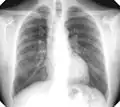

For uncomplicated silicosis, chest x-ray will confirm the presence of small (< 10 mm) nodules in the lungs, especially in the upper lung zones. Using the ILO classification system, these are of profusion 1/0 or greater and shape/size "p", "q", or "r". Lung zone involvement and profusion increases with disease progression. In advanced cases of silicosis, large opacity (> 1 cm) occurs from coalescence of small opacities, particularly in the upper lung zones. With retraction of the lung tissue, there is compensatory emphysema. Enlargement of the hilum is common with chronic and accelerated silicosis. In about 5–10% of cases, the nodes will calcify circumferentially, producing so-called "eggshell" calcification. This finding is not pathognomonic (diagnostic) of silicosis. In some cases, the pulmonary nodules may also become calcified.

Chest X-ray showing uncomplicated silicosis